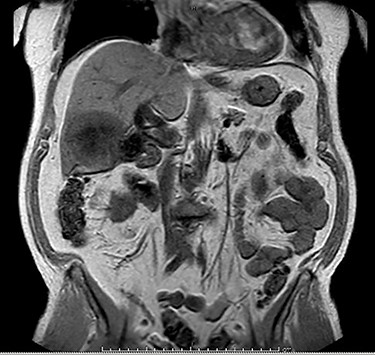

MRI demonstrated a 7.1 × 8.1 cm mass originating from the gallbladder that involved segments IVb, V, VI with areas of peripheral enhancement and central necrosis. Associated cholelithiasis was also noted. Figures 3–5 demonstrate the pertinent MRI findings.

MRI (axial view): 7.1 × 8.1 cm mass originating from the gallbladder involving segments IVb, V, VI with areas of peripheral enhancement and central necrosis.